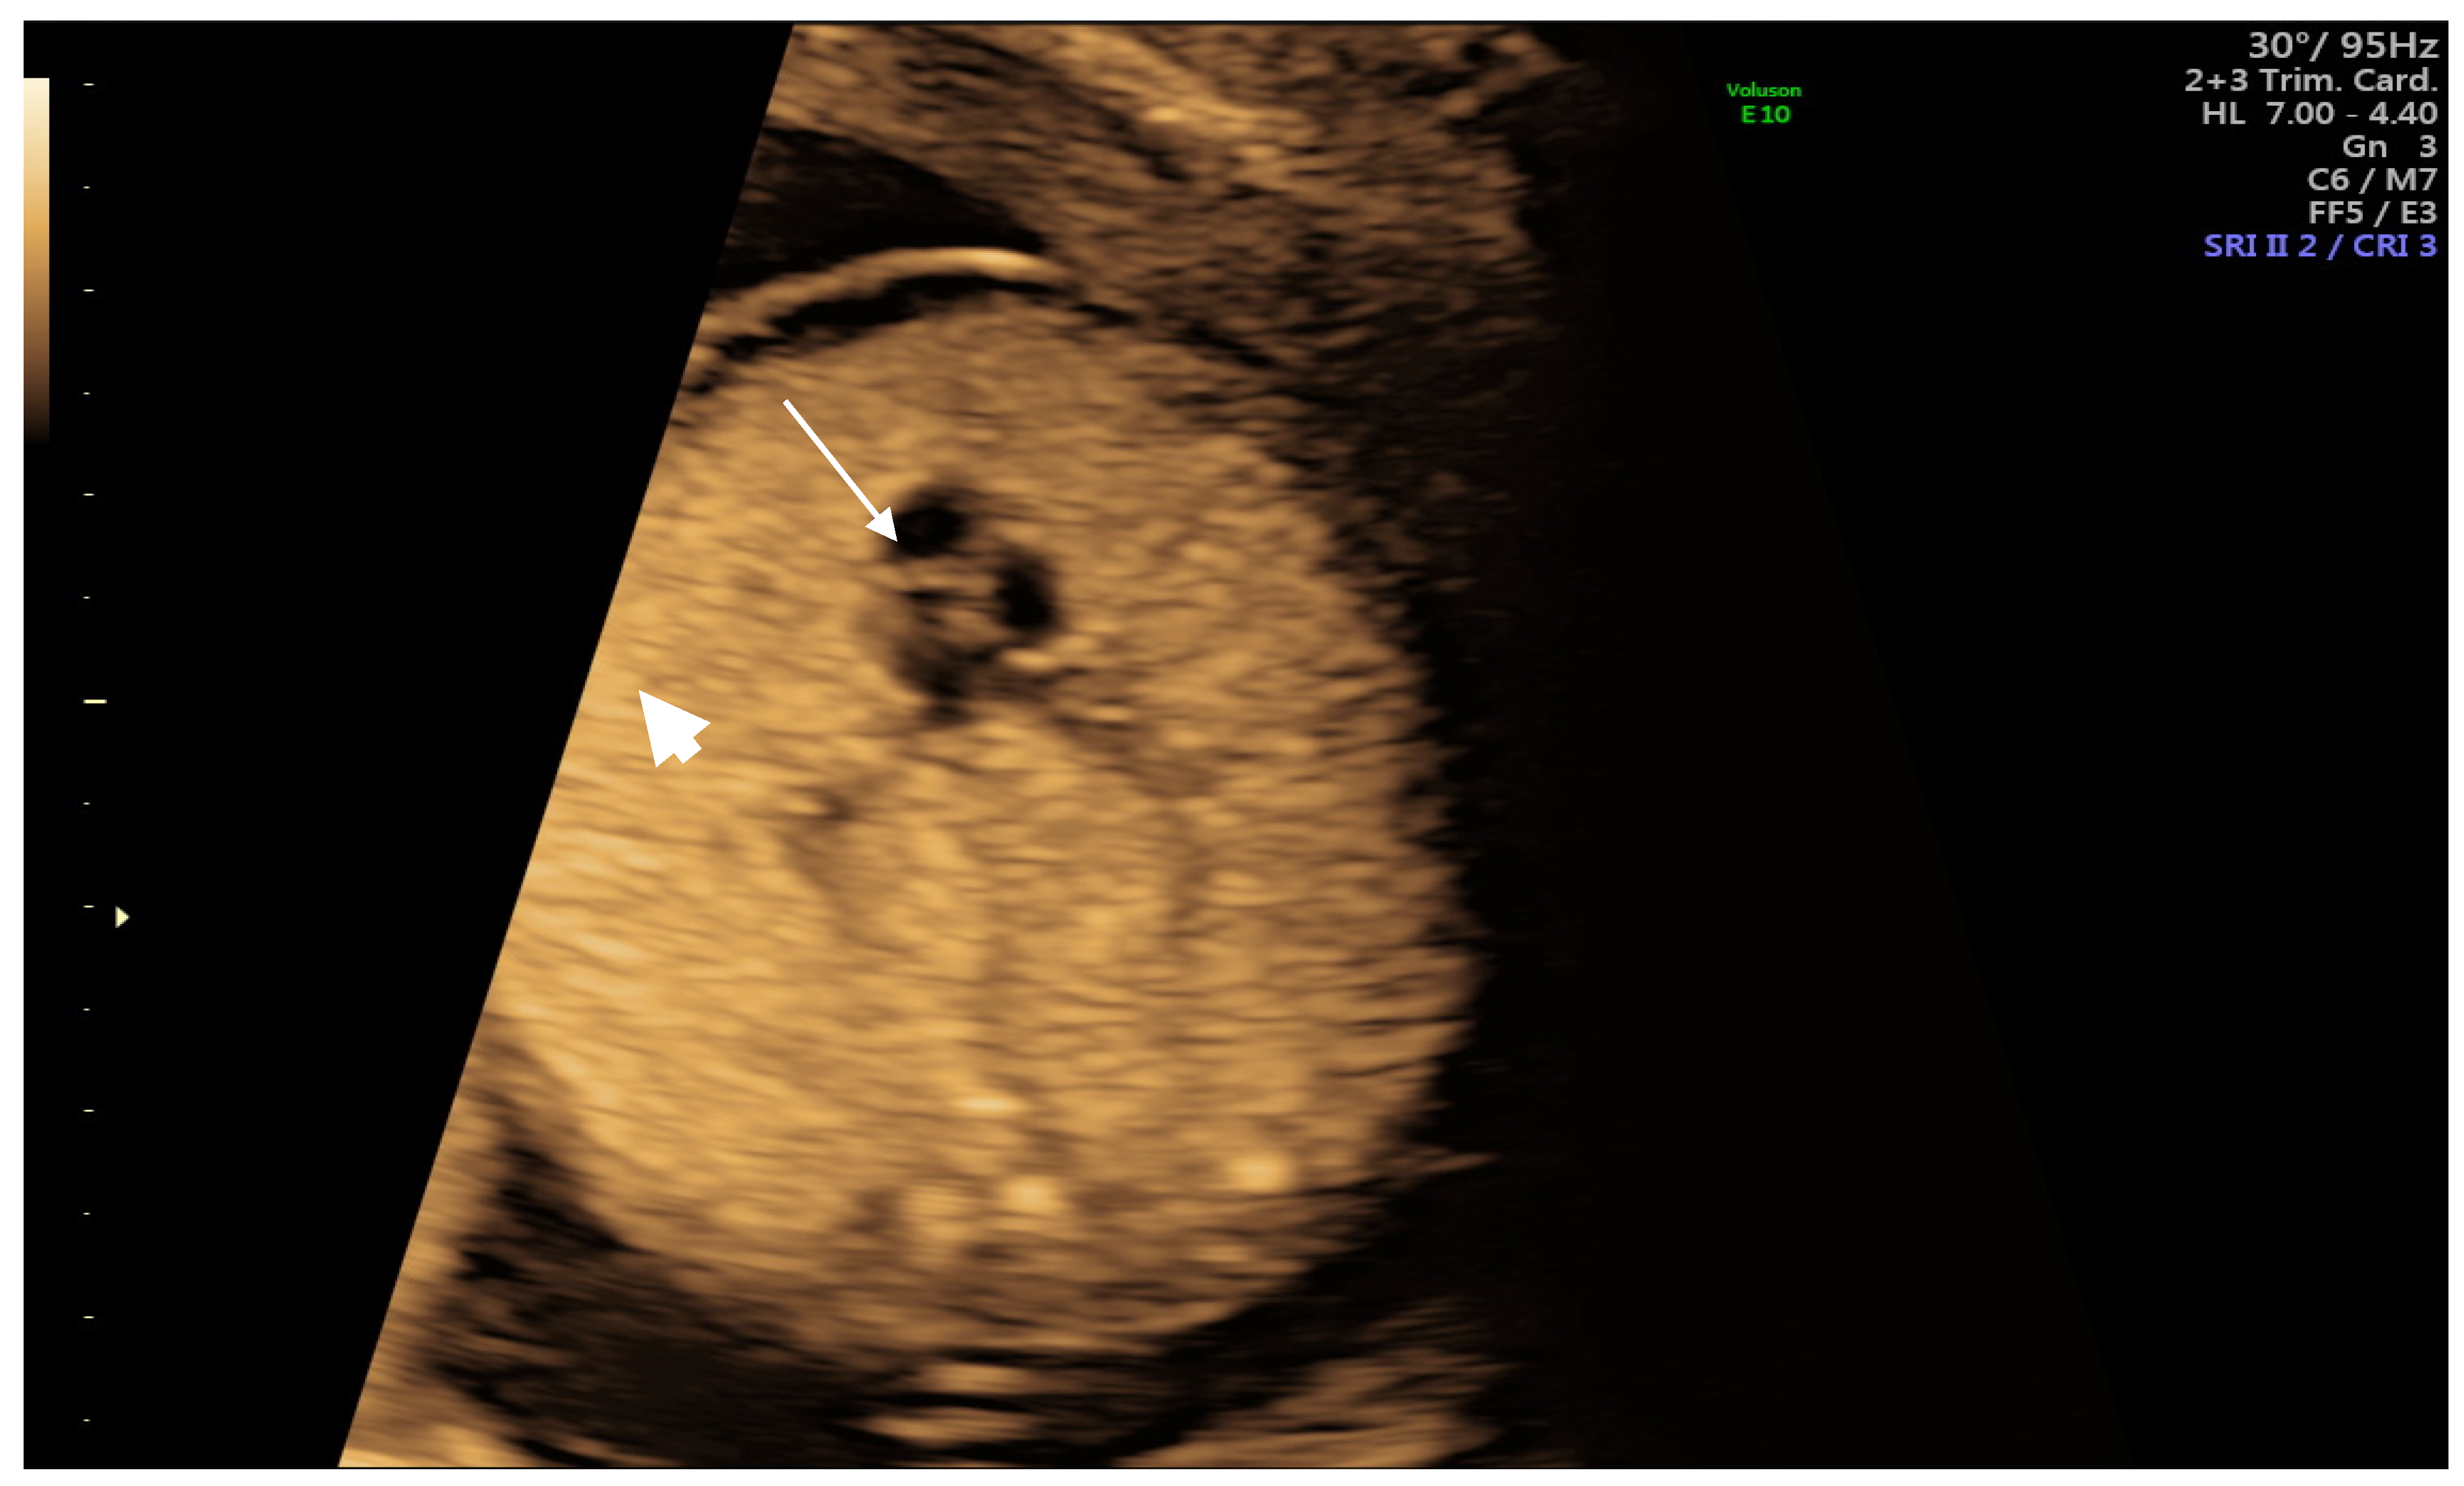

2. Case Report